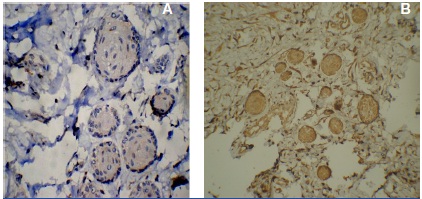

One of the retromolar tissue samples showed the presence of dental lamina rests which also were positive for all the markers providing an additional support to the study [Table/Fig-12,13, 14 a & b].

Ck19 staining in rests of serre 40x

Faint positivity to synaptophysin in rests of serre

CD99 and NSE positivity in the rests of serre